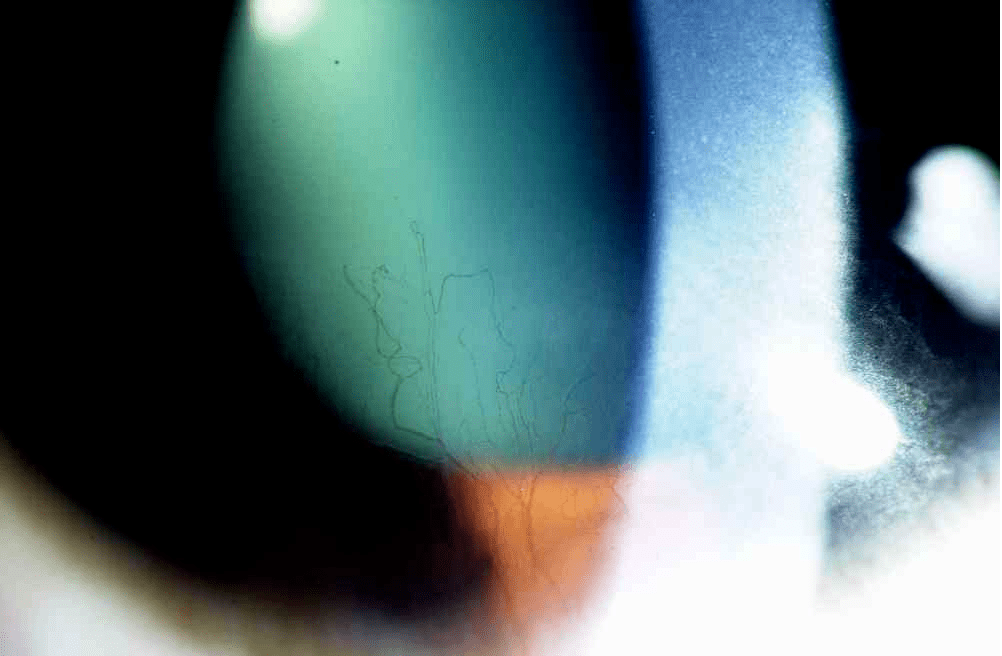

2.1窄光带照明法(或称光学切面法)

角膜

操作要点

• 光源亮度:中等至最强亮度

• 裂隙宽度:1mm窄裂隙,形成光学切面

• 裂隙夹角:30°~45°,可调如果想观察不同层次结构,可以拉大角度,产生组织层次分离效果

• 放大倍率:10x或者更高倍

• 观察:角膜、前房、晶状体,显示透明组织的厚度、病变深度